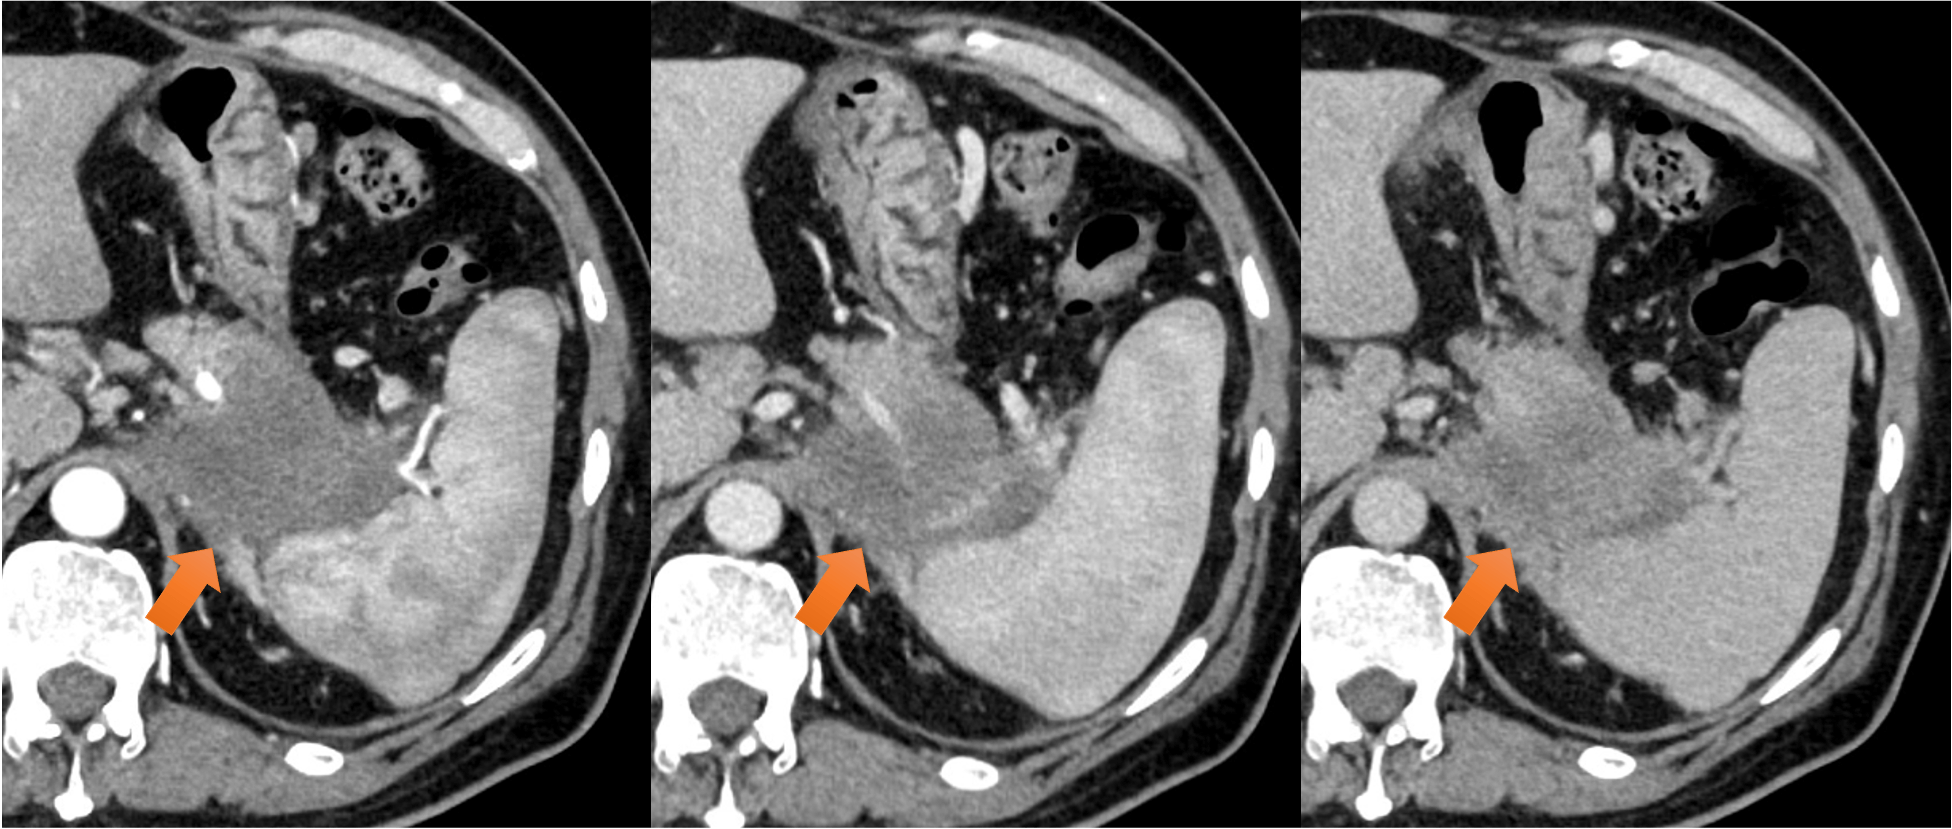

膵尾部癌のステージング目的の造影CT 膵尾部癌のステージング目的の造影CT 膵尾部癌のステージング目的の造影CT 2025-12-17 奈良県立医科大学附属病院Aquilion ONEキャノンメディカルシステムズ株式会社2025 詳細はこちら